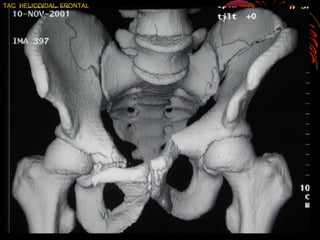

TAC HELICOIDAL FRONTAL

TAC/ACETÁBULO • PERMITE VISUALIZACIÓN MASDE DETALLADA LAS FRACTURAS , SUS DEPAZAMIENTOS SU IMPACTACIÓN MAS NO EN LAS TRANSVERSAS Y • LA CONGRUENCIA DEL TECHO ACETABULAR CON LA CABEZA. • LA RECONSTRUCCIÓN TRIDIMENCIONAL ES AUN MAS PRECISA Y PUEDE DESCOMPONER SE EN FRAGMENTOS RETIRANDO INCLUSO LA CABEZA DEL ACETÁBULO

• 40.

TAC EN FX.DE ACETÁBULO